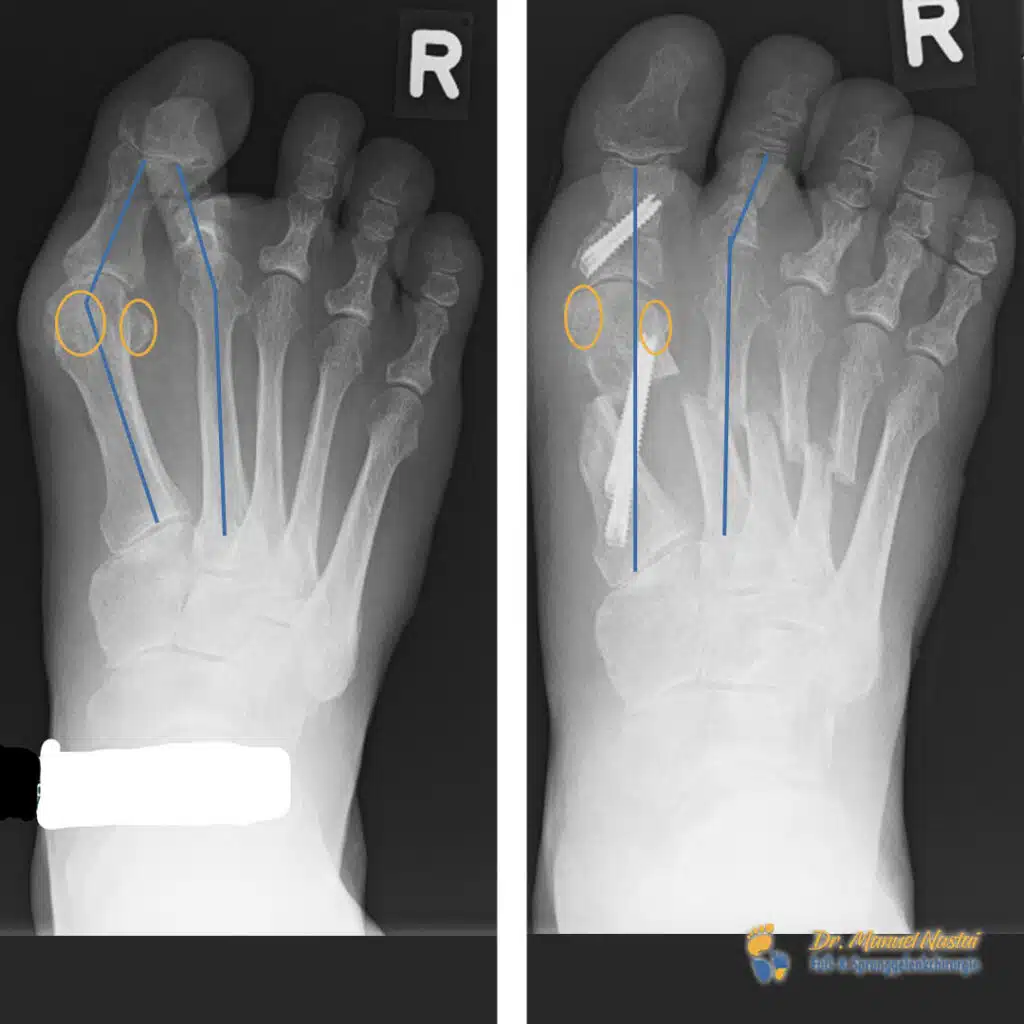

Links (präoperativ): Deutlicher Hallux valgus mit vergrößertem Intermetatarsalwinkel IMA 1–2 (blaue Linien markieren die Längsachsen von M1 und M2; die Spreizung ist klar erweitert). Die Sesambeine unter dem Großzehengrundgelenk (orange markiert) sind nach lateral verlagert und liegen nicht mehr zentral unter dem Metatarsalköpfchen – Ausdruck der Subluxation im MTP-I. Zusätzlich zeigt sich ein Hochstand / Beugerfixation der 2. Zehe: der 2. Strahl steht in Fehlstellung, was zur Überlastung/Transfermetatarsalgie neigt.

Rechts (postoperativ): Korrektur der Großzehenachse mit deutlich reduziertem IMA; die blauen Achsen von M1 und M2 verlaufen nun annähernd parallel (= Parallelisierung der Strahlen). Die Sesambeine (orange) sind rezentriert und wieder regelrecht unter dem ersten Metatarsalköpfchen positioniert. Die implantierten Schrauben sichern die Korrektur am 1. Strahl stabil. Die 2. Zehe zeigt eine aufgerichtete, belastungsfähige Stellung ohne Hochstand/Beugekontraktur.